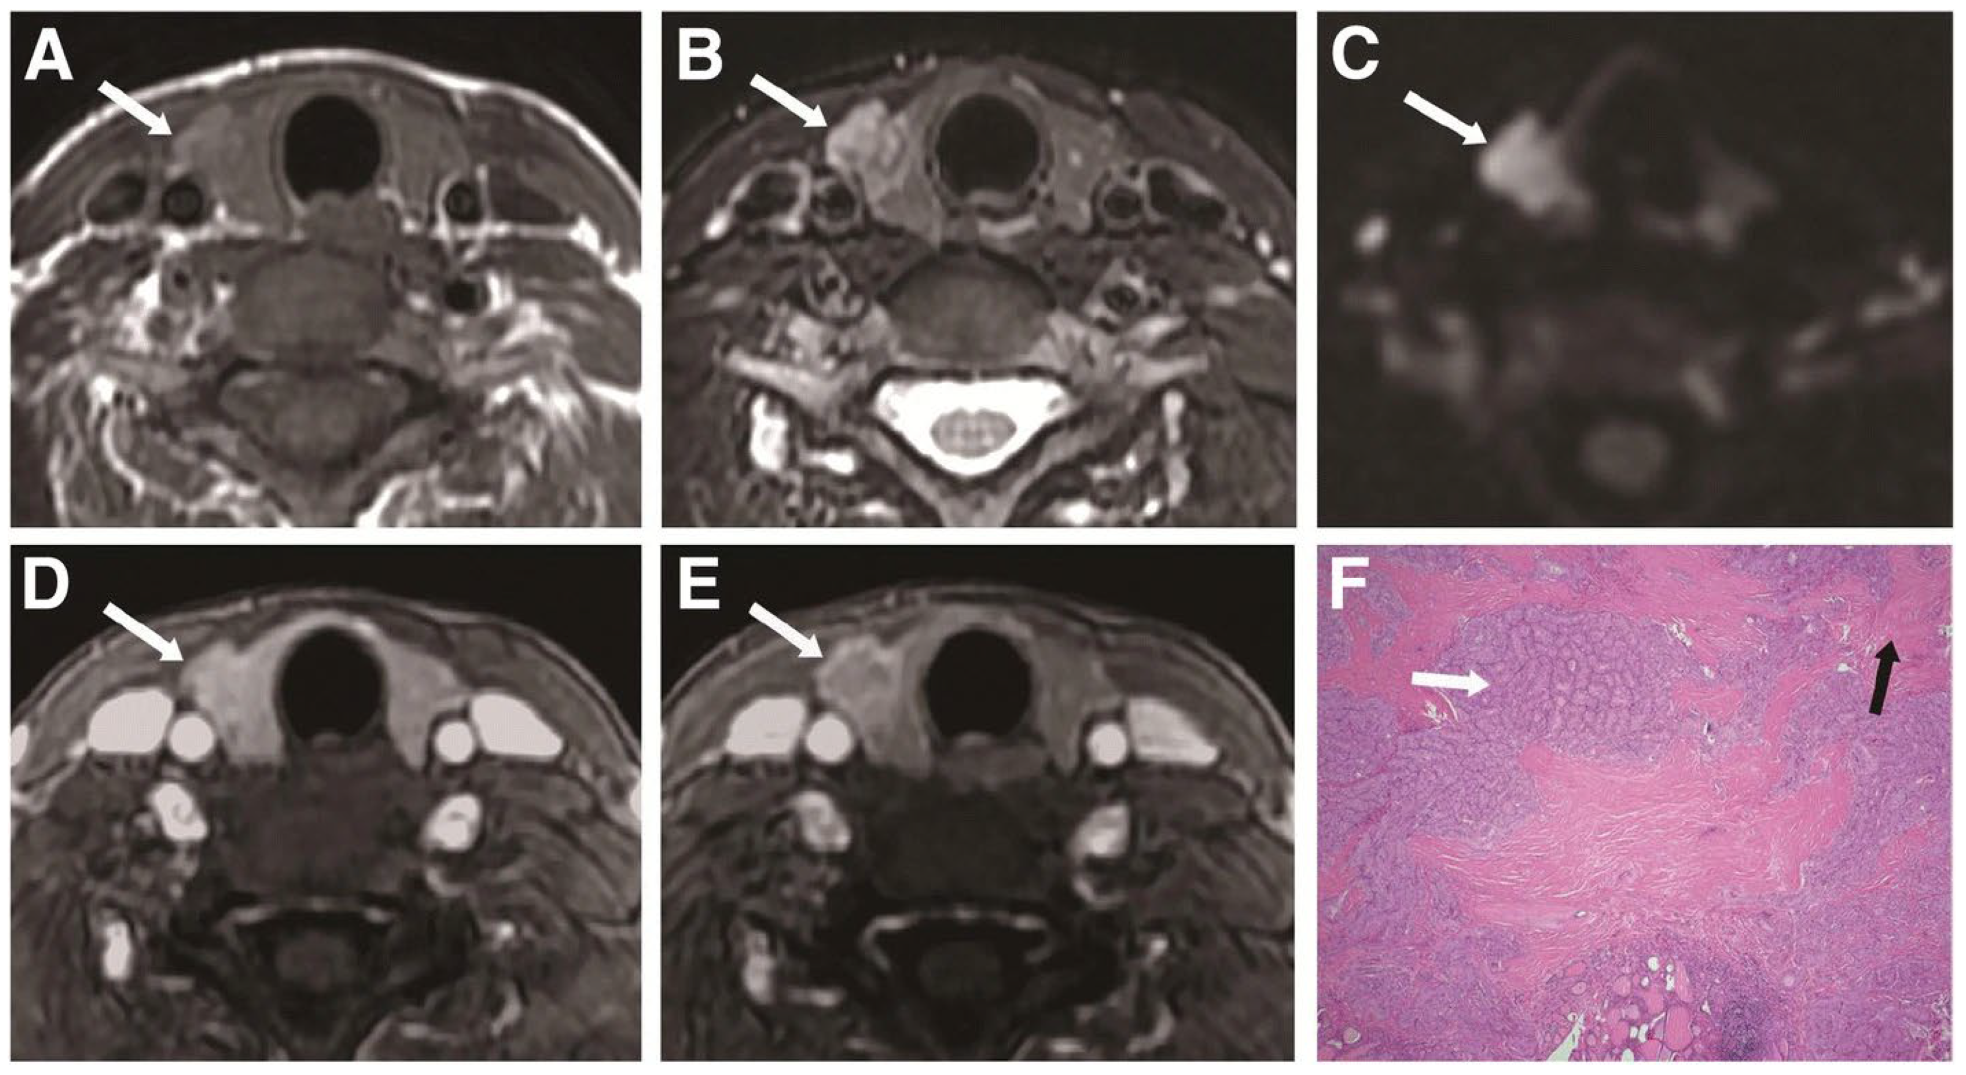

Figure 15.

MRI imaging of PTC in the right lobe: (A) Axial T1-weighted image showing a heterogeneous isointense nodule (long arrowhead) with patchy hyperintense signal (white arrow) in the left lobe. (B) Axial T2-weighted image showing a heterogeneous hyperintense nodule with cystic change (white arrow) in the left lobe. (C) Axial DWI image showing a hyperintense nodule (white arrow) with ADC value of 1.990 × 10−3 mm2/s. (D) Axial contrast-enhanced image showing a heterogeneous hyperintense lesion with a regular shape and clear margin in the left thyroid lobe during the early phase. (E) Axial contrast-enhanced image showing the pseudocapsule sign (white arrow) in the left thyroid lobe during delayed phase. (F) Histopathological hematoxylin and eosin (H&E, ×40) staining showing heterogeneous follicular hyperplasia with colloid and hemorrhage (white arrow). Retrieved from [94], under CC BY-NC 4.0 (Deed—Attribution 4.0 International—Creative Commons).